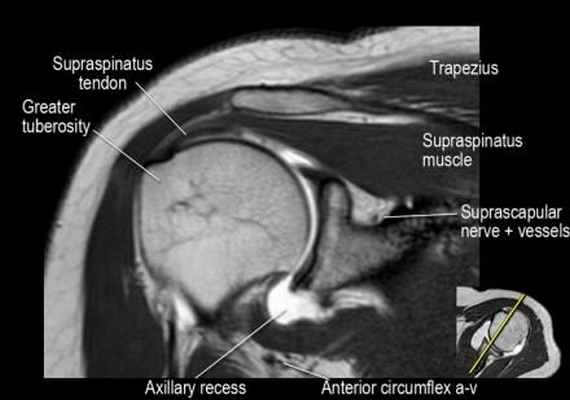

Нормальная корональная анатомия плечевого сустава и контрольный список

- обратите внимание на клюво-ключичную связку (coracoclavicular ligament) и короткую головку двуглавой мышцы (short head of the biceps).

- обратите внимание на клювоакромиальную связку (coracoacromial ligament).

- -

- обратите внимание на надлопаточный нерв и сосуды (suprascapular nerve and vessels)

- поищите импинджмент надостной мышцы за счет остеофитов в акромиально ключичном суставе или из-за утолщения клювовидноакромиальной связки.

- изучите верхний комплекс двуглавой мышцы и суставной губы, поищите подгубный карман илм SLAP-повреждение

- поищите скопление жидкости в подакромиальной сумке и повреждение сухожидия надостной мышцы

- поищите частичный разрыв сухожилия надостной мышцы в месте его прикрепления в виде кольцевидного повышения сигнала

- изучите область прикрепления нижней плече-лопаточной связки. Изучите нижний комплекс суставной губы и связок. Поищите HAGL-повреждение (humeral avulsion of the glenohumeral ligament).

- поищите повреждение сухожилия подостной мышцы

- обратите внимание на небольшое повреждение Хилл-Сакса